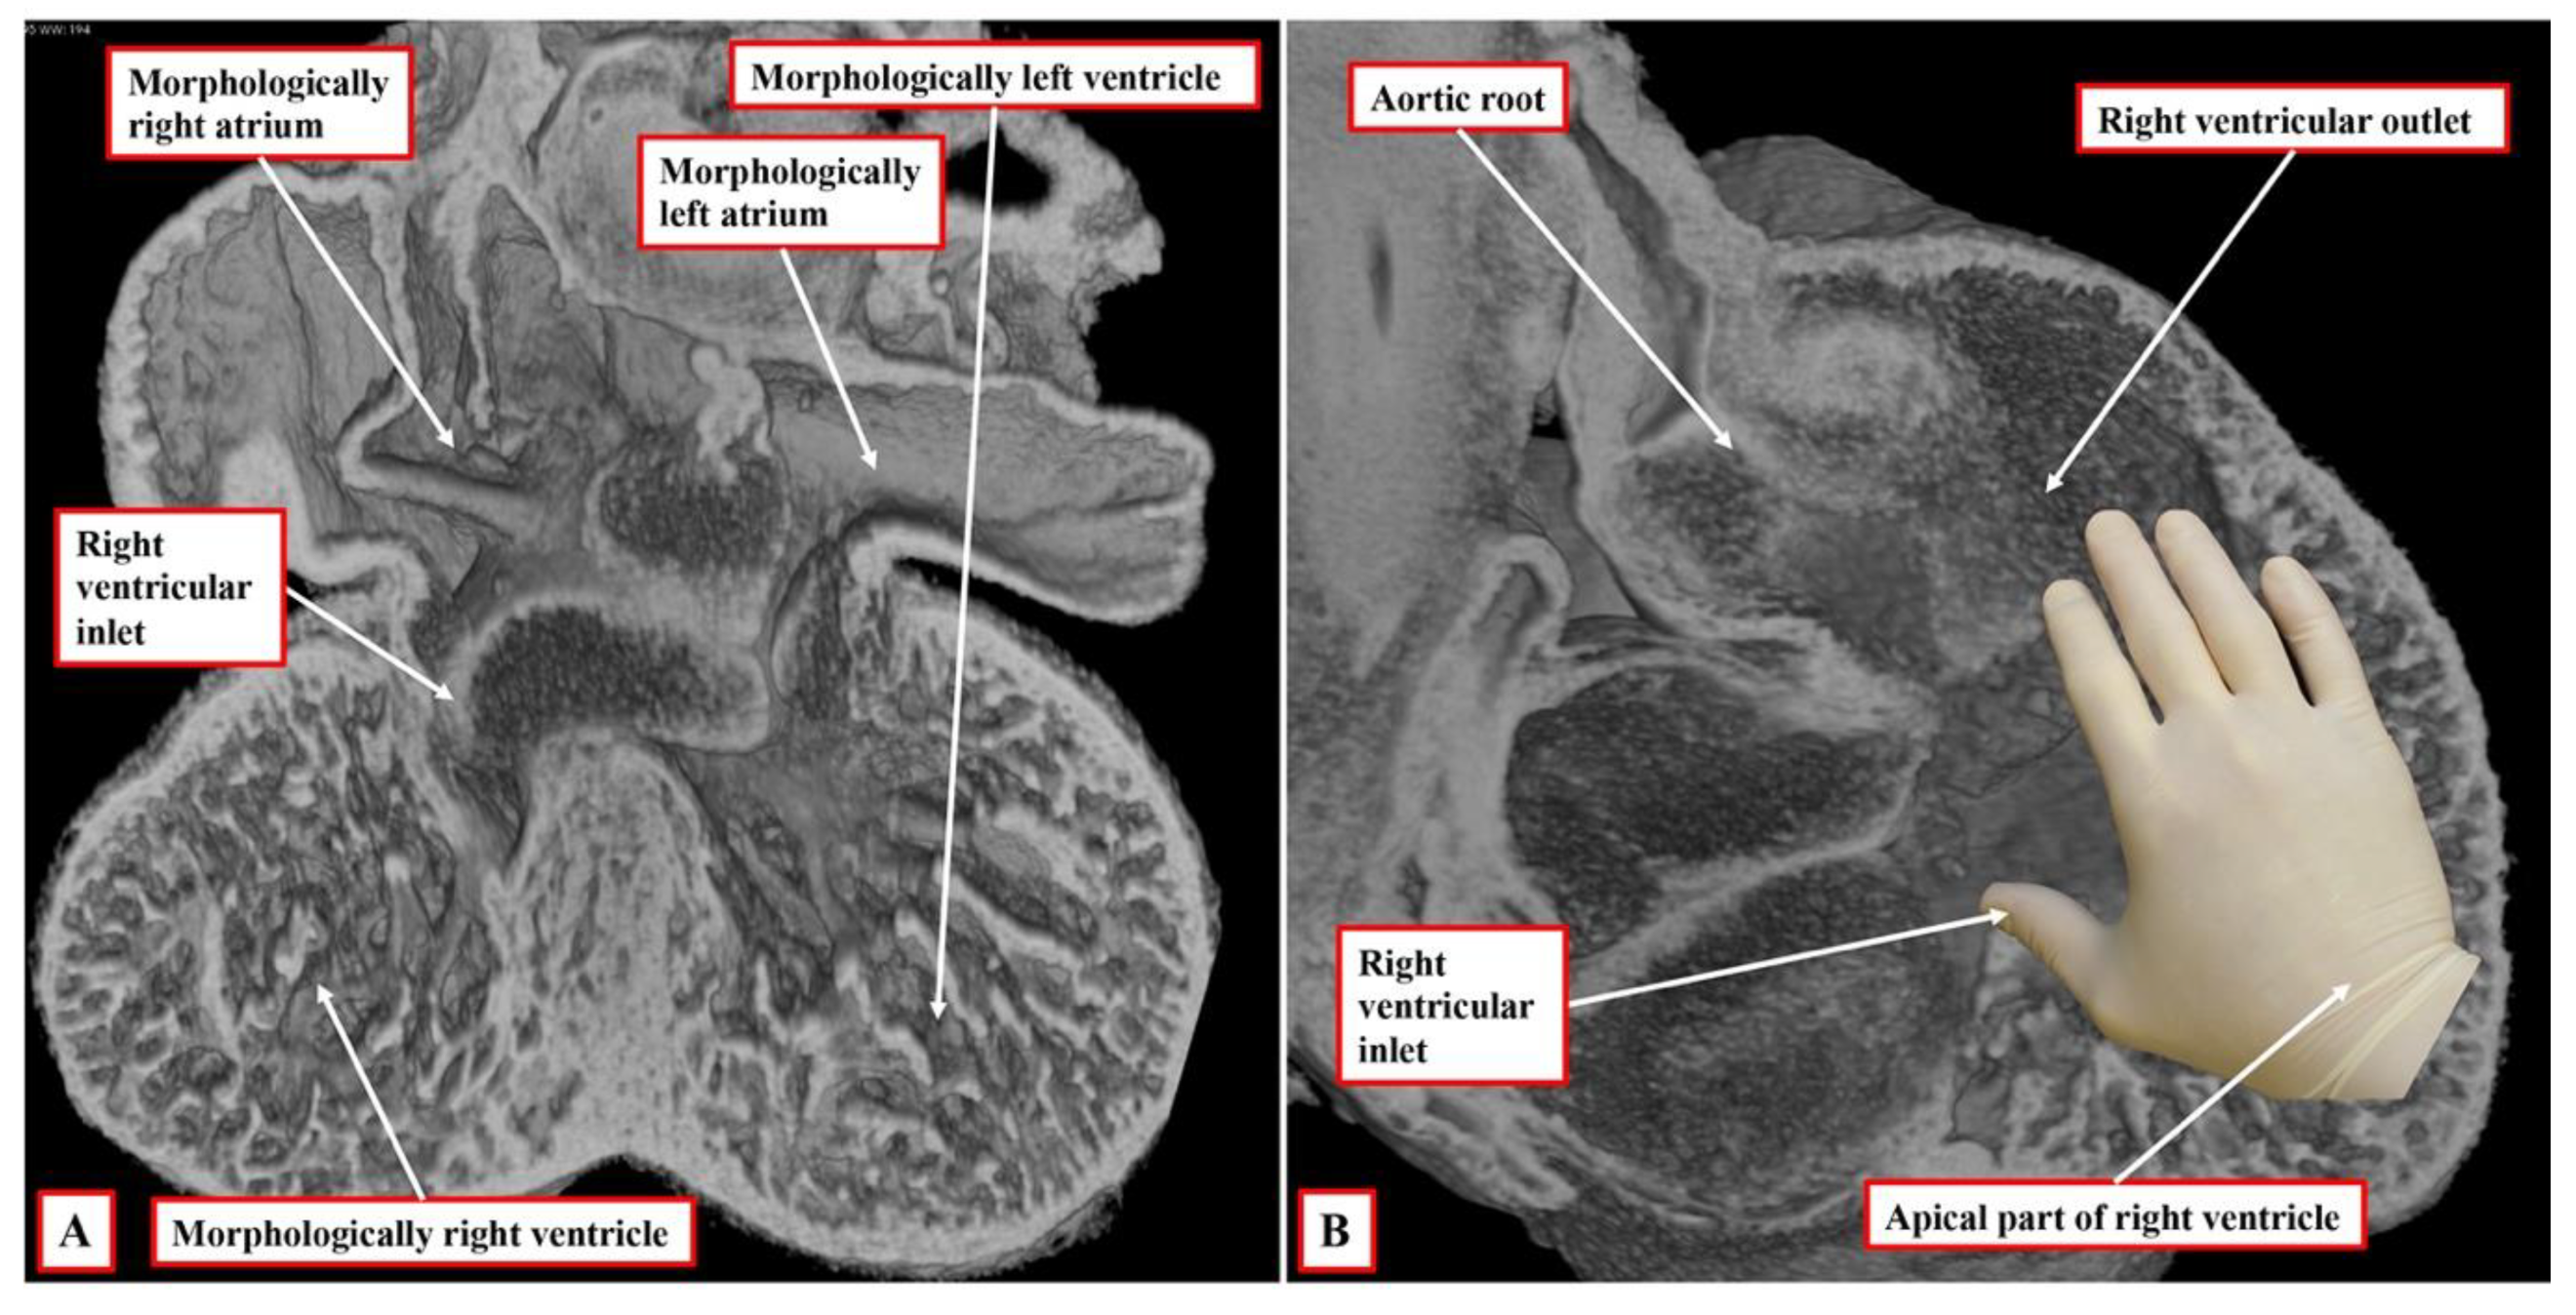

It is the next stage of development that sets the scene for the establishment of ventricular topology. Simply by expansion of the atrioventricular canal, the right ventricle achieves its own inlet component. In the murine heart, this process occurs between embryonic days 10.5 and 11.5 (Compare

Figure 2 and

Figure 3). In the human heart, the period encompasses the fifth and sixth weeks of development subsequent to fertilisation. Once it has achieved its own inlet (

Figure 3A), even though it continues to support the entirety of the outflow tract, the right ventricle can be recognised to have achieved right-handed topology (

Figure 3B). It is the morphologically right ventricle, by convention, that is used as the arbiter of ventricular topology or chirality. The concept depends on the ability, figuratively speaking, to place the palmar surface of the hands on the septal surface of the right ventricle. The thumb is placed in the tricuspid valve, the wrist occupies the apical trabecular component, and the fingers extend into the ventricular outflow tract. In the normal heart, once the right ventricle has developed its own inlet (

Figure 3B), it is only the palm of the right hand that fits the septal surface of the morphologically right ventricle (

Figure 4A). In the setting of congenitally corrected transposition, in contrast, which is itself the consequence of the development of discordant atrioventricular connections, and when the atrial chambers are in their usual positions, it is only the palmar surface of the left hand that can be placed on the septal surface (

Figure 4B).

It follows, of course, that the left hand could be placed on the septal surface of the morphologically left ventricle in the setting of right-handed topology and the right hand when there is left-handed topology. Convention, nonetheless, has dictated that the right ventricle should be used as the landmark. It also follows that, should congenitally corrected transposition be found in the setting of mirror-imaged atrial arrangement, then the ventricular mass, almost without exception, shows right-handed topology. The caveat, however, is “almost without exception”. On very rare occasions, the ventricular topology is disharmonious with the fashion in which the cavities of the atrial chambers are joined to the ventricles. It is the feature of the flow pathways across the atrioventricular junctions, of course, which is used in the sequential segmental approach to define the segmental connections. Within the segmental approach, however, the so-called “alignments” must be inferred from the information provided within the segmental set. Thus, those with {S,D,*} are presumed to have concordance. This means that, in transposition {S,D,D}, the segmental notation indicates that the atrial and ventricular chambers are joined together in a morphologically appropriate fashion. In transposition {S,L,L}, the segmental notation would indicate that the atrial chambers are joined to morphologically inappropriate ventricles. This system, however, fails to account for disharmony between the morphology of the segments and the connections between them.